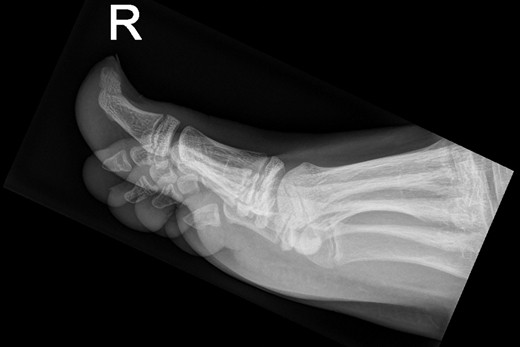

Patiënte B, een 49-jarige vrouw, bezoekt de huisarts met een pijnlijke granulomateuze zwelling, subunguaal aan de mediale zijde van de linker hallux [figuur 3]. Histologisch onderzoek door de huisarts vermeldt acanthose en hyperkeratose, zonder duiding van maligniteit. Het röntgenonderzoek toont het beeld van een subunguale exostose en de patiënte krijgt een verwijzing naar de orthopedisch chirurg voor excisie [figuur 4].

Een X-voet (driekwartopname) van patiënte B. De exostose is zichtbaar op de eindfalanx van digitus 1.